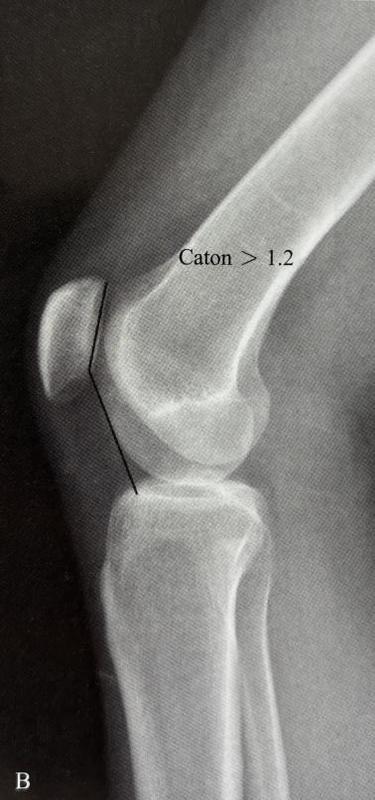

髕骨脫位(patelladislocation)是指髕骨由于多種因素脫離正常的運動軌跡向外側(cè)脫位,是最常見的急性膝關(guān)節(jié)損傷之一,占急性膝關(guān)節(jié)損傷的3%,常見于兒童和青少年。在過去的幾十年,由于參加體育運動的人數(shù)越來越多,導(dǎo)致髕骨脫位的發(fā)病率越來越高,每100,000人中就有5.8~77.8個人患有髕骨脫位,且女性較男性的發(fā)病率更高。髕骨脫位的病因眾多,通常與骨性異常或軟組織病變有關(guān)。骨性異常1.高位髕骨(patellaalta):指由于髕韌帶長度過長(>52mm)導(dǎo)致髕骨在矢狀面的垂直高度增加,是一種先天性的異常。高位髕骨是復(fù)發(fā)性髕骨脫位的高危因素,在屈膝早期階段,髕骨進入股骨滑車溝延遲,與股骨滑車的接觸面減少,骨性穩(wěn)定作用減弱,容易發(fā)生脫位。Caton指數(shù)>1.2可協(xié)助診斷。2.低位髕骨(patellainfera):指髕骨在矢狀面的垂直高度降低,大多數(shù)為獲得性,可以由外傷導(dǎo)致,也與不恰當?shù)闹委熡嘘P(guān)。根據(jù)病因,低位髕骨可分為:先天性、創(chuàng)傷性、制動性、麻痹性和醫(yī)源性。Caton?0.6,Insall<0.8可明確診斷。3.滑車發(fā)育不良:指患者的股骨滑車沒有發(fā)育成正常的凹面的解剖形狀,而是成為平坦的甚至是凸起的形狀?;颊叩墓晒腔嚋系赘叨犬惓#诨嚱诵纬晒切酝蛊?,突出于股骨干前方皮質(zhì),導(dǎo)致髕骨不得不越過滑車近端的骨性凸起才能進入滑車,從而導(dǎo)致髕骨脫位。20世紀90年代,H.Dejour首次提出采用膝關(guān)節(jié)純側(cè)位X線片評估滑車發(fā)育不良的方法,將滑車發(fā)育不良分成4型。A型:純側(cè)位片僅有交叉征,軸位片可見滑車較正常平坦。B型:純側(cè)位片可見交叉征和突起征,軸位片可見滑車外側(cè)面凸起或平坦。C型:純側(cè)位片同時可見交叉征和雙線征,但沒有突起征。軸位片可見滑車外側(cè)面凸起,內(nèi)側(cè)面發(fā)育不良。D型:純側(cè)位片同時可見交叉征、雙線征和突起征,軸位片可見滑車外側(cè)面突起,內(nèi)側(cè)滑車發(fā)育不良,甚至形成“懸崖征”(cliffsign)。4.脛骨結(jié)節(jié)過度外偏:目前脛骨結(jié)節(jié)-股骨滑車間距(tibialtubercle-trochleargroovedistance,TT-TG)通常在膝關(guān)節(jié)伸直位進行CT掃描測量,第一個掃描層面通常為通過股骨滑車關(guān)節(jié)軟骨的首個掃描平面,第二個層面通過脛骨結(jié)節(jié)的近端。TT-TG的正常參考值為<12mm,TT-TG>20mm的患者,可在MPFL重建術(shù)的基礎(chǔ)上聯(lián)合脛骨結(jié)節(jié)截骨術(shù)。軟組織病變1.多韌帶松弛癥:多發(fā)關(guān)節(jié)松弛癥(generalizedlaxity)和膝關(guān)節(jié)局部松弛癥(localizedjointlaxity)是髕股關(guān)節(jié)不穩(wěn)定的常見易患因素之一。Beighton診斷標準:滿分9分,成年人≥4分,兒童?6分即可診斷多發(fā)關(guān)節(jié)松弛癥。2.髕內(nèi)側(cè)穩(wěn)定結(jié)構(gòu)損傷:內(nèi)側(cè)髕骨股骨韌帶(medialpatellofemoralligament,MPFL)是限制髕骨外移的一級穩(wěn)定結(jié)構(gòu),是髕骨穩(wěn)定的最重要的軟組織穩(wěn)定結(jié)構(gòu)。MPFL斷裂后不僅會導(dǎo)致髕骨外移的顯著增加,同時還將增大股骨滑車外側(cè)面的壓力,導(dǎo)致膝前痛、骨性關(guān)節(jié)炎等疾病。根據(jù)遺傳病因?qū)W,髕骨脫位可分為復(fù)發(fā)性髕骨脫位、習(xí)慣性髕骨脫位和先天性髕骨脫位。復(fù)發(fā)性髕骨脫位:復(fù)發(fā)性髕骨脫位是由于急性髕骨脫位發(fā)展而來,常常伴隨內(nèi)側(cè)髕骨股骨韌帶損傷,并可能伴有髕骨內(nèi)側(cè)關(guān)節(jié)軟骨或股骨外髁骨軟骨骨折,通??勺孕袕?fù)位。多數(shù)患者自訴在受傷時有“髕骨錯位感”,臨床檢查可發(fā)現(xiàn)膝關(guān)節(jié)內(nèi)側(cè)支持帶區(qū)域壓痛、膝關(guān)節(jié)內(nèi)側(cè)血腫以及髕骨外推恐懼試驗陽性。習(xí)慣性髕骨脫位:習(xí)慣性髕骨脫位又稱隨意性髕骨脫位。表現(xiàn)為每次屈膝時均發(fā)生髕骨脫位,完全伸膝時復(fù)位,患者通常沒有疼痛主訴。其發(fā)病機制是由于股四頭肌的短縮,因此若手法強行限制髕骨脫位,膝關(guān)節(jié)的屈曲會受限。在習(xí)慣性髕骨脫位的患者中,常合并膝外翻(valgus)、股骨滑車發(fā)育不良(trochleardysplasia)、伸膝裝置短縮、脛骨結(jié)節(jié)外偏(tibialtuberclelateralization)、股骨和脛骨扭轉(zhuǎn)畸形(femoralandtibialtorsionaldeformity)等。固定性髕骨脫位:固定性髕骨脫位包括先天性髕骨脫位以及由外傷導(dǎo)致的急性髕骨脫位發(fā)展而來。前者是出生時即出現(xiàn)的髕骨脫位(通常在10歲以前發(fā)現(xiàn));后者是因外傷導(dǎo)致髕內(nèi)側(cè)穩(wěn)定結(jié)構(gòu)完全失去穩(wěn)定功能。固定性髕骨脫位的患者,無論膝關(guān)節(jié)是伸直還是屈曲,髕骨始終處于脫位狀態(tài)且不能復(fù)位。與習(xí)慣性髕骨脫位相比,復(fù)發(fā)性髕骨脫位的患者往往有明顯的外傷史,習(xí)慣性髕骨脫位的患者可能伴隨先天性的骨性異常以及軟組織病變。復(fù)發(fā)性髕骨脫位可通過保守治療恢復(fù)髕骨穩(wěn)定性,但二次損傷可能導(dǎo)致髕骨再次脫位,每次均可通過手法復(fù)位;而習(xí)慣性髕骨脫位可在每次屈膝時出現(xiàn),僅在完全伸膝時可復(fù)位,強行手法復(fù)位可能會導(dǎo)致膝關(guān)節(jié)活動受限。因此在臨床診斷時,需詳細詢問病人的病史,并結(jié)合查體謹慎辨別兩種髕骨脫位。髕骨脫位的治療方案可分為保守治療和手術(shù)治療。對于初發(fā)的急性髕骨脫位,可采取保守治療?;颊咄ㄟ^3周的鉸鏈式伸直位支具固定,配合理療和藥物治療可緩解腫脹和疼痛,3周后可在專業(yè)康復(fù)師的指導(dǎo)下進行康復(fù)訓(xùn)練:ROM訓(xùn)練恢復(fù)關(guān)節(jié)活動度、VMO強化訓(xùn)練和核心肌群訓(xùn)練增強髕骨穩(wěn)定性以及髂脛束拉伸訓(xùn)練減少髕骨外側(cè)牽拉力。6周后門診復(fù)查,若保守治療無效,無法維持復(fù)位或反復(fù)脫位者則建議手術(shù)治療。手術(shù)治療要根據(jù)患者存在的主要病理因素設(shè)計手術(shù)方案,即使是同一種脫位類型,在不同患者可能會接受不同的手術(shù)方案。手術(shù)方案包括兩大類。一是近端力線矯正術(shù),二是遠端力線矯正術(shù)。近端力線矯正術(shù)包括:股骨遠端截骨術(shù)、滑車成形術(shù)、外側(cè)支持帶松解或延長術(shù)以及MPFL重建術(shù)等;遠端力線矯正術(shù)包括脛骨結(jié)節(jié)截骨術(shù)、髕腱外側(cè)半內(nèi)移術(shù)、脛骨近端截骨術(shù)等。多數(shù)髕骨脫位患者需要接受MPFL重建術(shù)。可選擇不同的移植物代替原本的MPFL,自體移植物包括自體半腱肌腱、股薄肌腱、內(nèi)收肌腱、股四頭肌腱、髕韌帶、髂脛束及闊筋膜等,異體移植物包括異體骨-髕腱復(fù)合體、異體脛前肌腱或半腱肌腱等,或人工韌帶。臨床多選用自體半腱肌腱作為移植物。髕骨脫位是臨床青少年人群較為常見的膝關(guān)節(jié)疾病,明確其分型對于治療方案的選擇和治療效果至關(guān)重要。在手術(shù)治療前要認真、個體化地分析導(dǎo)致患者髕骨脫位的病理因素。手術(shù)治療要圍繞引起患者髕骨脫位的主要病理因素設(shè)計手術(shù)方案,同一類型的髕骨脫位也可能通過不同術(shù)式解決。